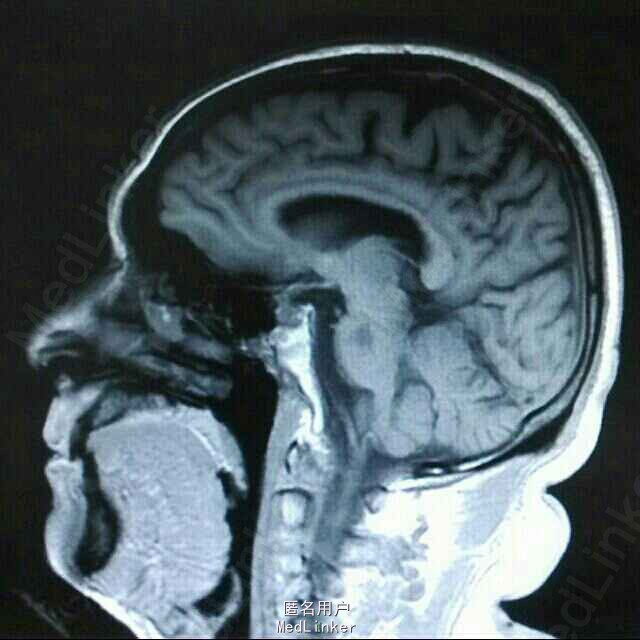

查体:BP 136/84mmHg,抬腿右下肢较左侧差,余无明显异常。 辅检:6-8 D-D 1.87,FIB 7.15,ALT 38,AST 46,GGT 37,LDL-C 4.38,铁蛋白 320,CRP 96.7,ESR 70,尿酮体1+ 6-15 PLT 469,ALT 53,GGT 50,ESR 38,D-D 0.59 血糖监测:早餐后高 彩超多普勒:升主动脉较宽,左室舒张功能减低;双侧颈动脉粥样硬化斑形成。 经颅多普勒:双侧颈内动脉、颈外动脉、左侧颈总动脉血流速度减慢;左侧锁骨下动脉、右侧大脑中动脉、大脑前动脉、左侧颈内动脉虹吸部管腔呈收缩状态;左侧颈内动脉虹吸部管腔重度狭窄;各检查动脉管腔应硬化。 头部MR、脑动脉造影MRA:脑干右侧11*12mm梗塞灶;腔隙性脑梗塞;脑萎缩;双侧额部顶部硬膜下积液;左侧椎动脉起始段及椎动脉-基底动脉汇合段管腔中度狭窄,双侧颈总、颈内外动脉、双侧大脑前中后动脉多发中-重度狭窄,动脉粥样硬化表现。

诊断:脑梗塞;高血压病3级 极高危;糖尿病 2型;动脉粥样硬化;高脂血症;慢性胃炎 治疗:依达拉奉、马来酸桂哌齐特、丹森川穹嗪注射,小牛血清去蛋白注射液;硝苯地平缓释片;阿司匹林肠溶片;阿托伐他丁钙片;阿卡波糖片。